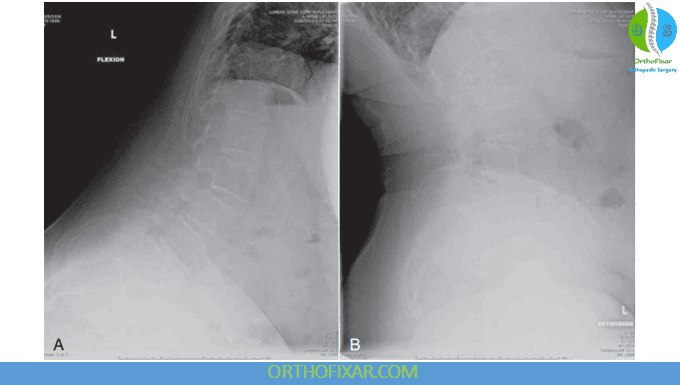

Motion Views

Dynamic lumbar spine X-rays (flexion and extension lateral views) can reveal abnormal spinal motion or instability. These motion views are especially helpful in diagnosing spondylolisthesis or subtle segmental instability. In some cases, anteroposterior side-bending views are also obtained.